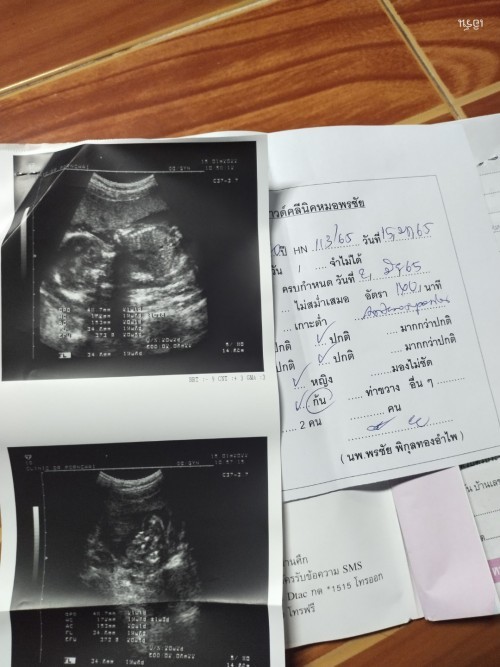

บ้านนี้ 18week หันโชว์คูมหมอไปเลยค้าบบบบ🥰